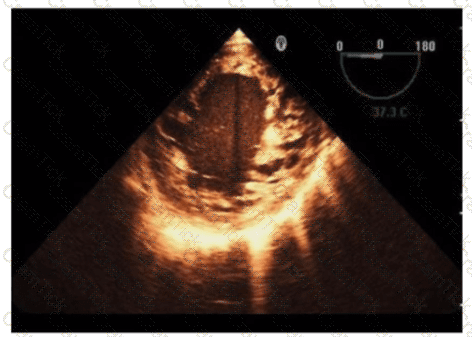

Which diagnosis is most likely confirmed by echocardiography in a 65-year-old female presenting with new onset chest pain associated with ST segment elevation on the electrocardiogram and angiographically normal coronary artenes?

Which is the most likely abnormality represented in these images from a 48-year-old man with shortness of breath?